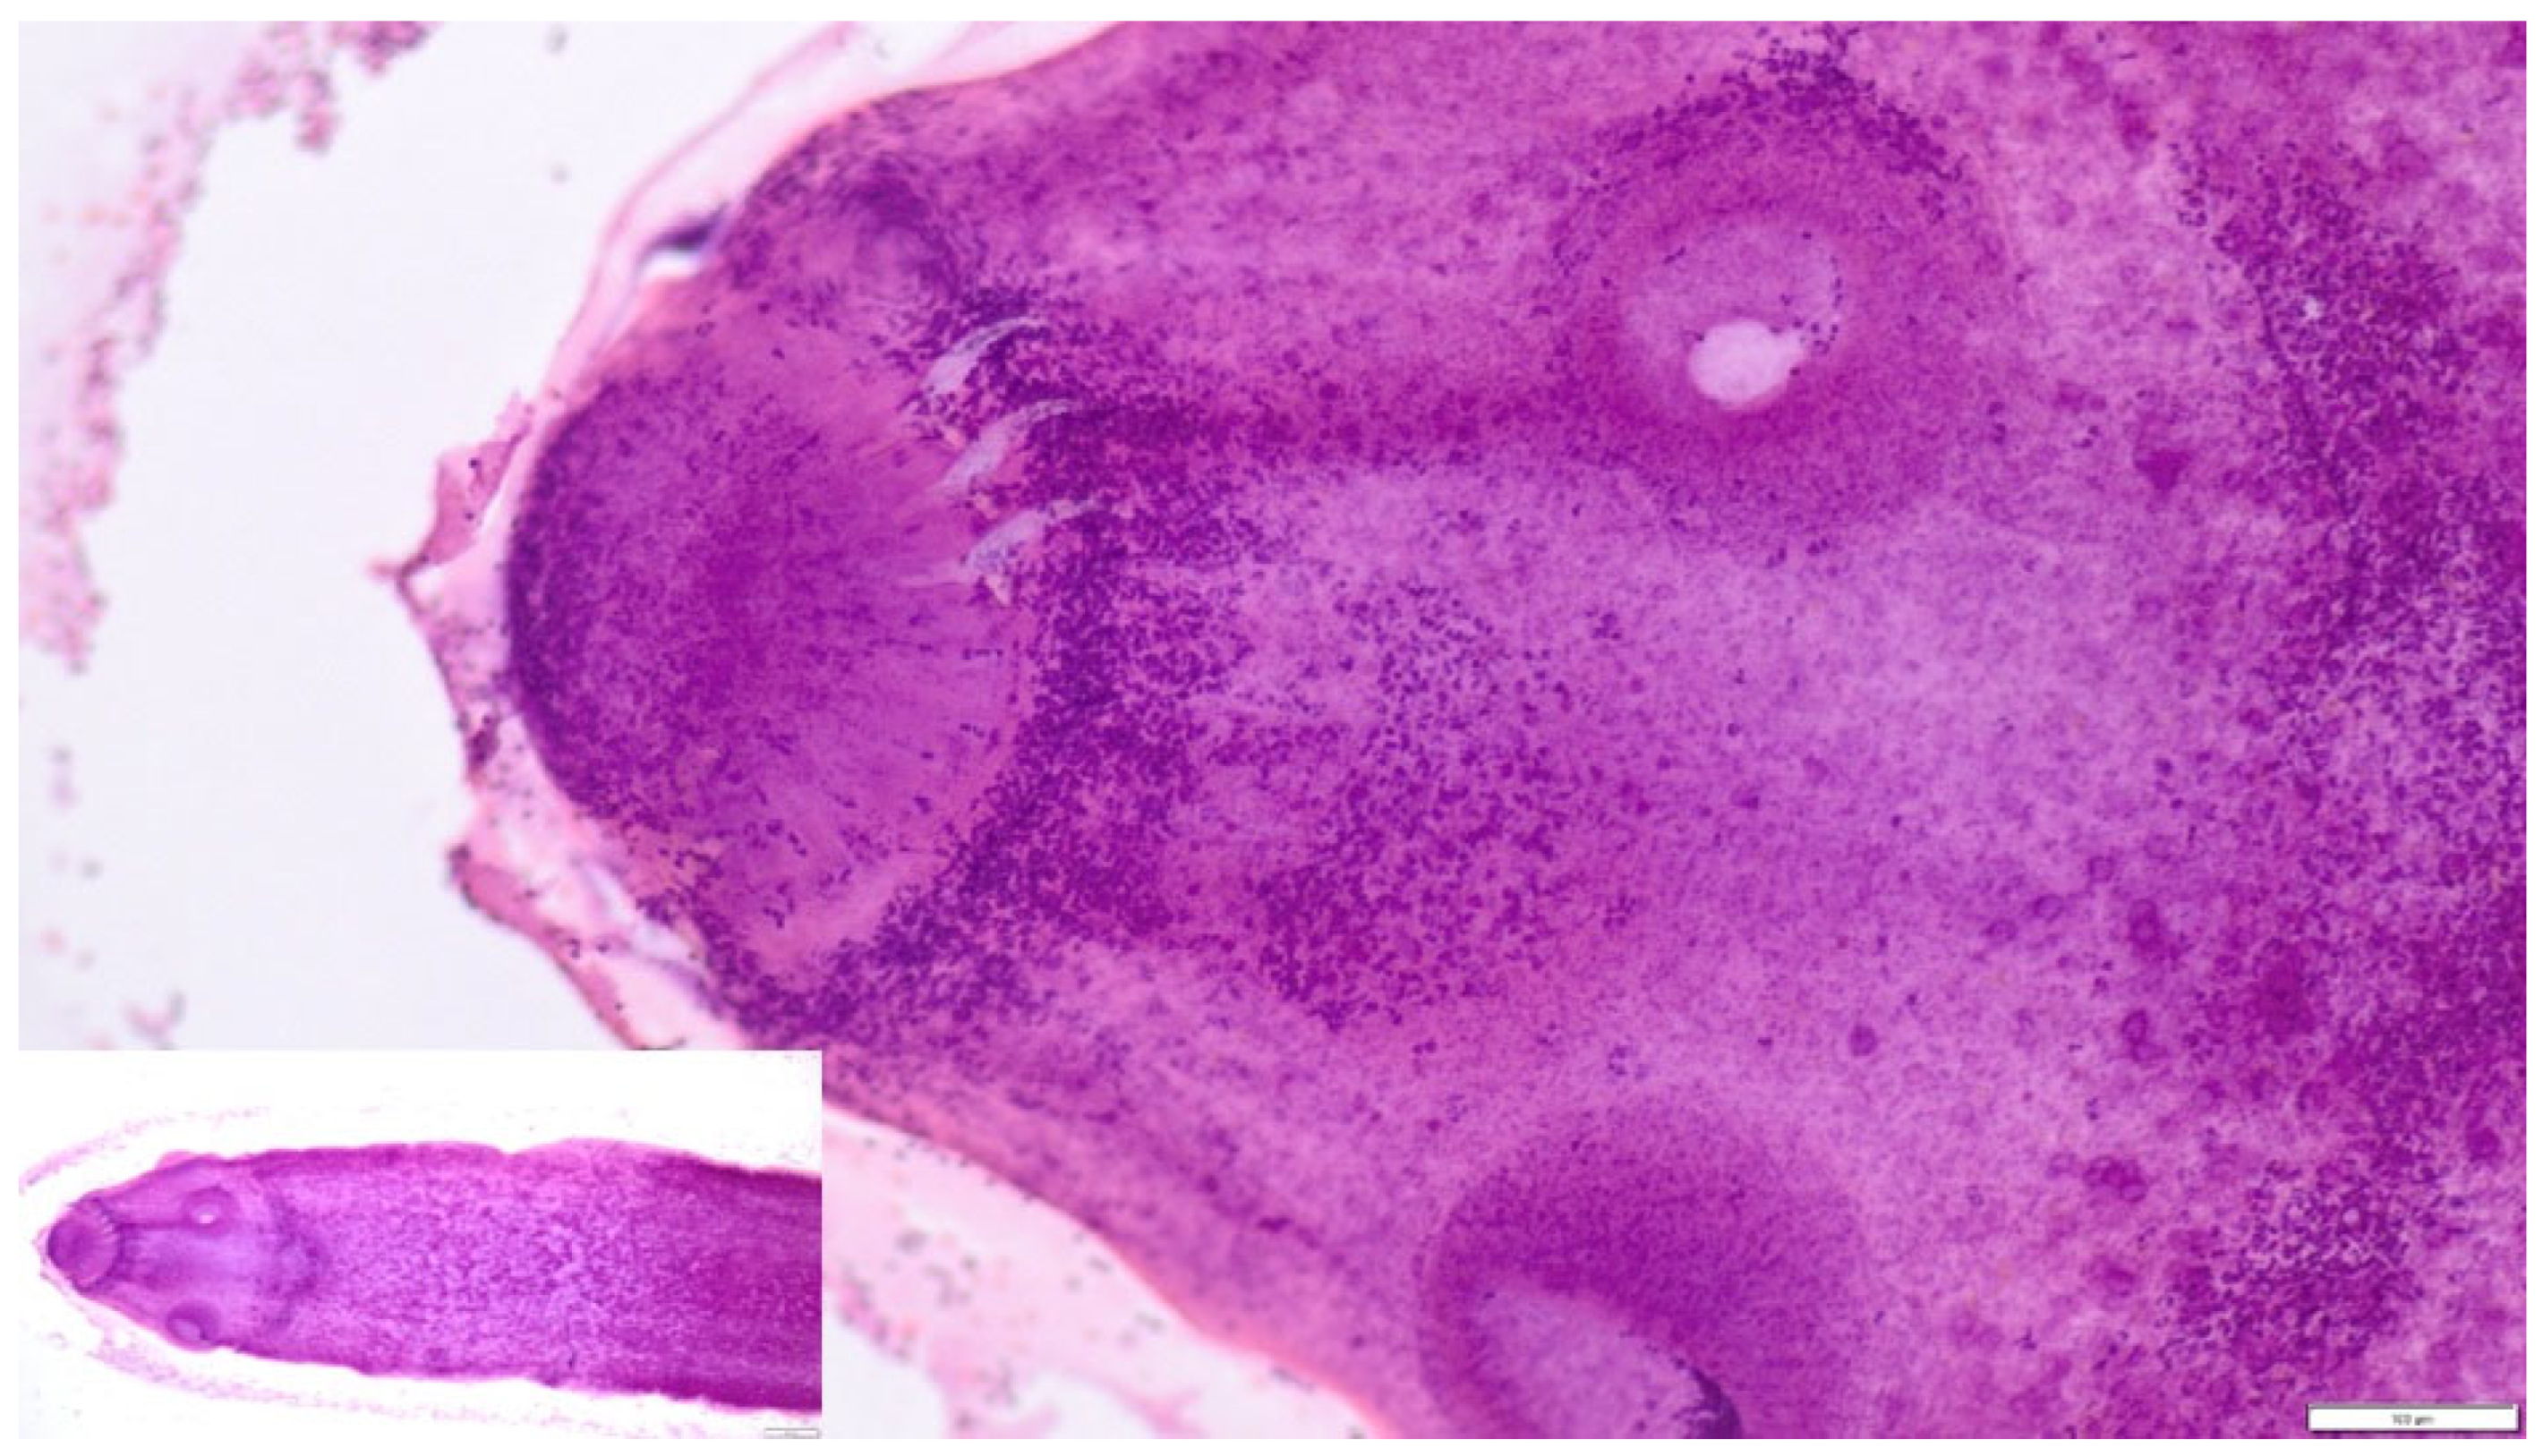

3.3. Histopathological Findings

3.4. Parasitological Findings